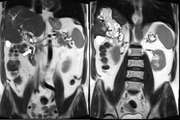

Functional Endoscopic Sinus Surgery in Management of Pott’s Puffy Tumor in a Pregnant Woman: A Clinical Case Report and Literature Review 1403/12/27 - 11:09